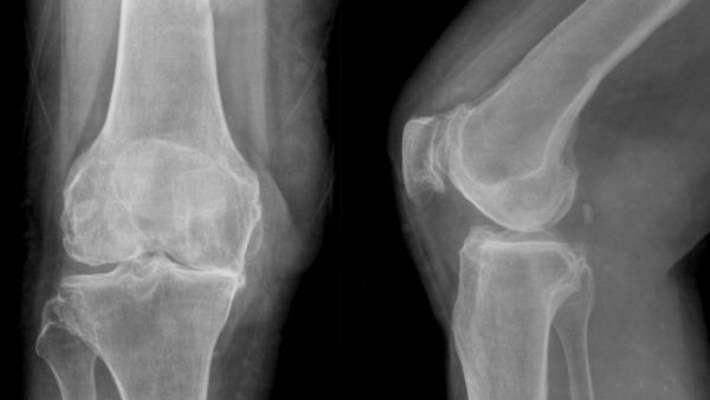

Pek çok bozukluk eklem ağrısına neden olabilir. Görüntüleme testleri kesin tanı koyulmasında yardımcı olabilir.

• Röntgen: Röntgen sonuçları avasküler nekrozun erken evrelerinde genellikle normal görünür. Ama hastalığın ileri evrelerinde gerçekleşen kemik değişimlerini genellikle gösterebilir.